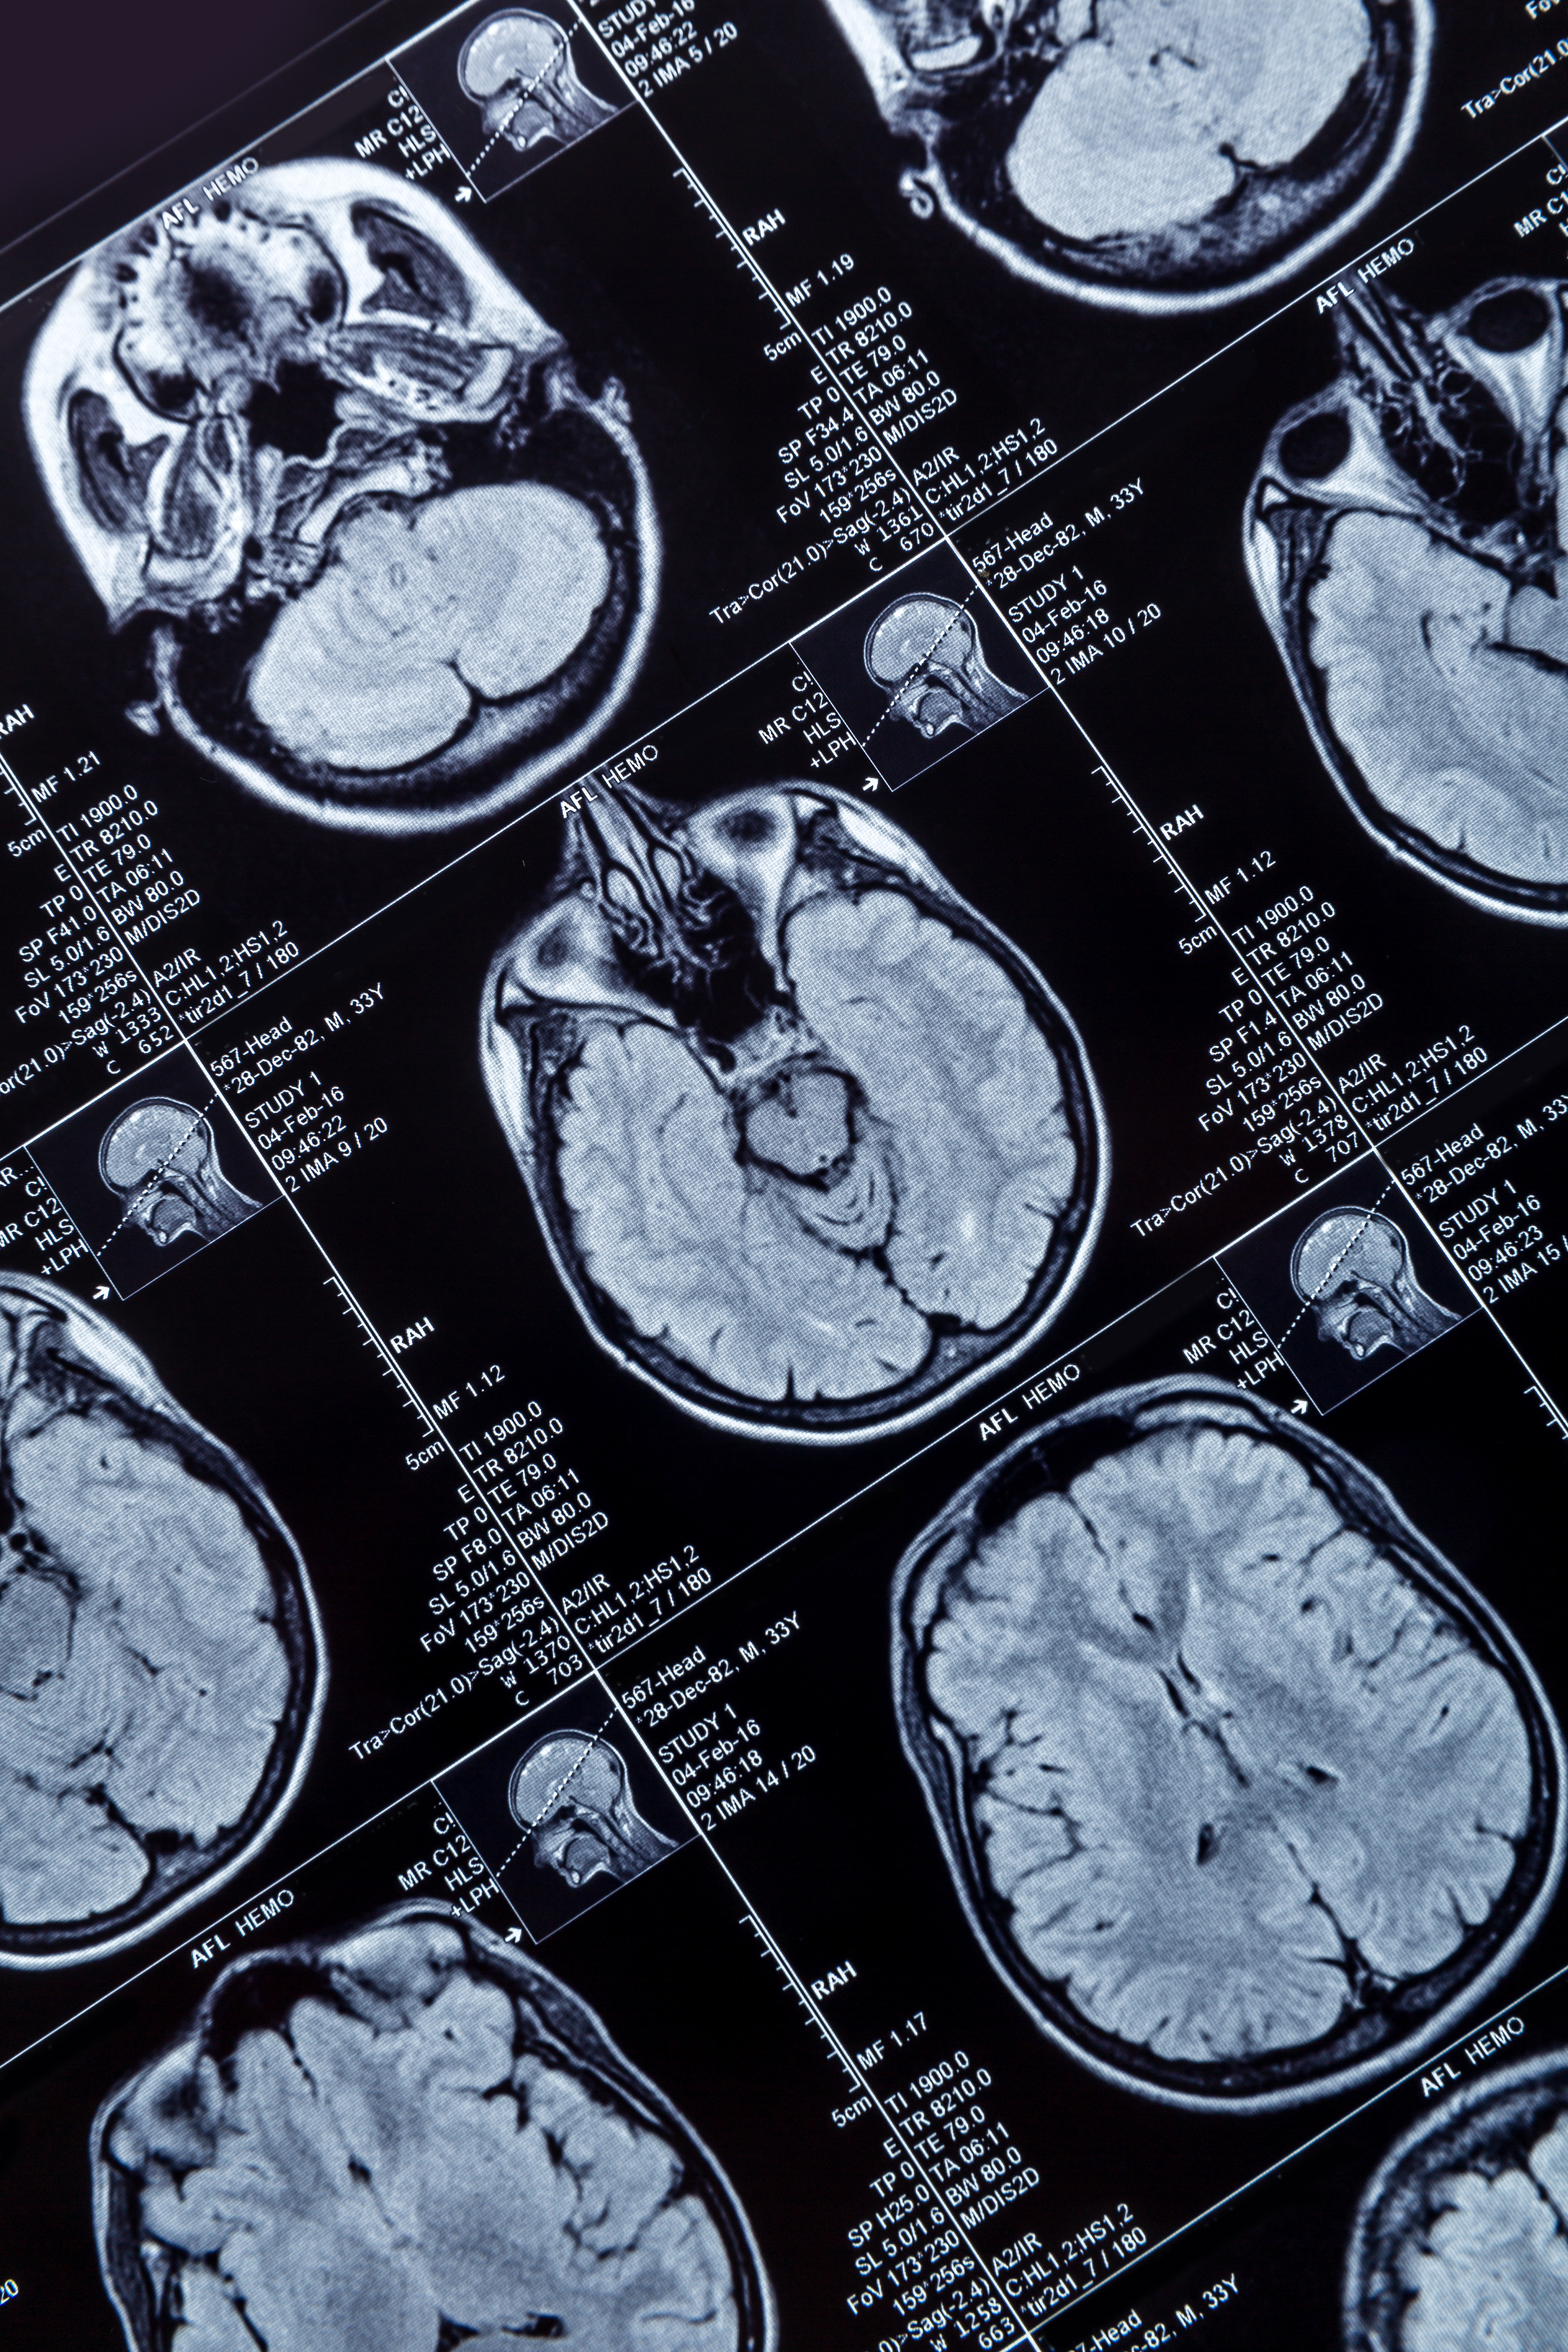

Using an abbreviated screening protocol for contrast-enhanced breast MR works just as well in terms of specificity and sensitivity as a full protocol, according to a new study published online in Academic Radiology.

Dr. Lars Grimm of Duke University Medical Center.Limiting screening MRI to high-risk women (20% or more lifetime risk) helps maintain cost-effectiveness, but the benefit to women at intermediate risk (often due to breast tissue density) is lost. A shorter breast MRI protocol could allow for lower cost and more rapid throughput, making breast MR a useful alternative screening modality for women with dense breast tissue, according to the authors (Acad Radiol, July 4, 2015).

For this pilot study, three breast imagers evaluated 48 breast MR exams (24 normal, 12 benign, and 12 malignant) selected from a high-risk screening population. The exams were presented in three viewing protocols:

- Abbreviated 1: Included fat-saturated precontrast T2-weighted, precontrast T1-weighted, and first-pass T1-weighted postcontrast sequences

- Abbreviated 2: Included the abbreviated 1 protocol plus a second-pass T1-weighted postcontrast sequence

- Full: Included nonfat-saturated T1-weighted, fat-saturated T2-weighted, precontrast T1-weighted, and three or four dynamic postcontrast sequences

The researchers found no statistically significant difference in sensitivity between the abbreviated 1 or abbreviated 2 protocols and the full protocol. There also was no statistically significant difference in specificity between the three protocols.